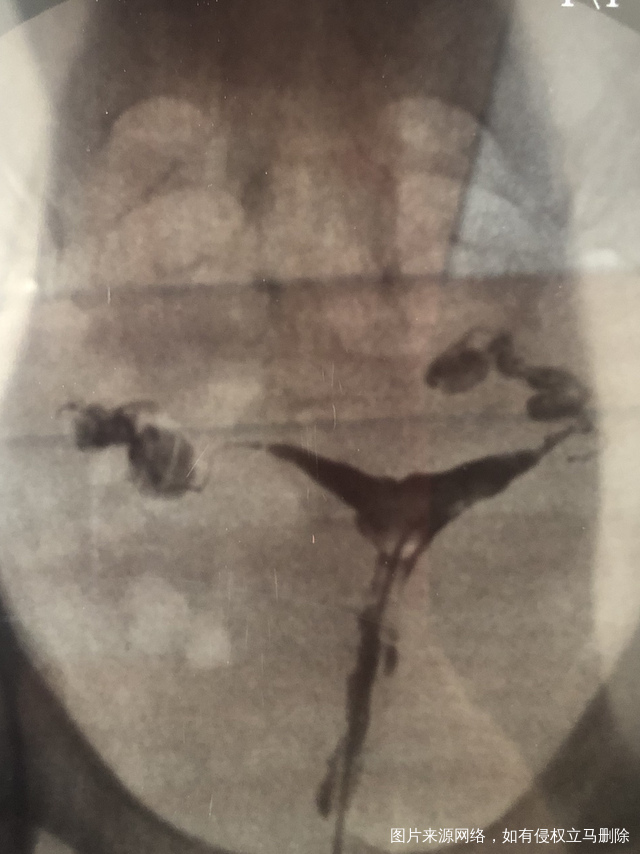

做完输卵管造影第六天了小腹还是感觉沉甸甸的如

可以热敷腹部,如果有发热,腹痛加剧,白带量多,有异味,随时就医